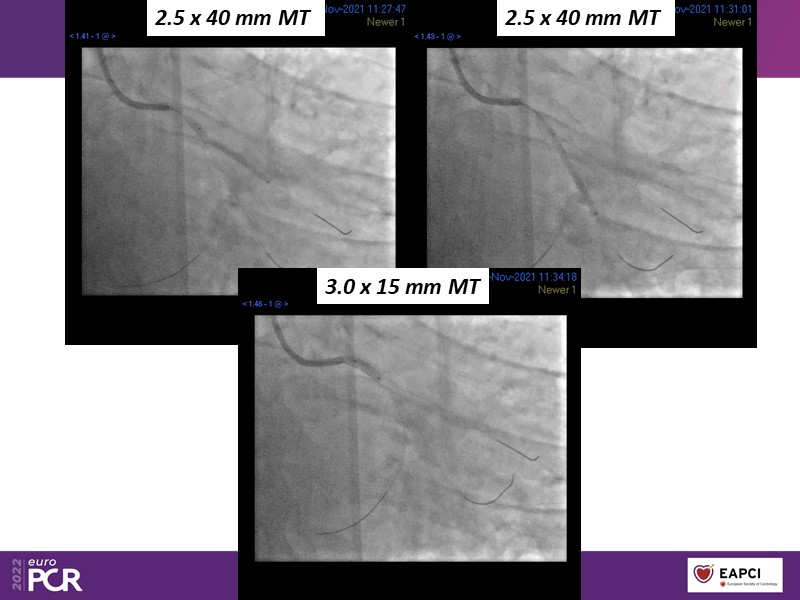

Alexandre Abizaid, Marco Valgimigli, Fazila Malik, Luca Testa, Patrick W. Serruys, Damiano Regazzoli, Kumar Prathap, and Sandeep Basavarajaiah take turns in this session to discuss two innovative technologies: a stent platform with nanotechnology and a novel drug-coated balloon (DCB). These novel technologies both have unique features that could change daily practice and improve outcomes.

- To find out more about the application and mechanism of a sirolimus coated balloon for coronary artery disease treatment with case presentations in complex settings

- To understand how useful is a DES and DCB stent platform in complex coronary artery disease settings with case demonstrations and follow-up in diabetes mellitus